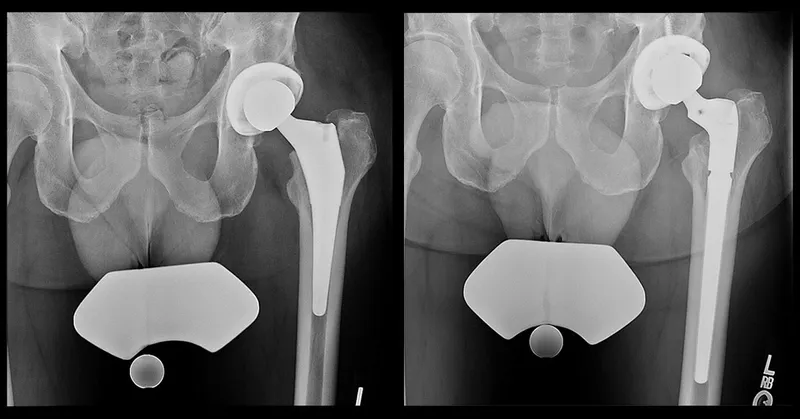

Revision Arthroplasty: Intra-op Challenges & Solutions - Battlefield Tactics

- Exposure & Implant Removal:

- Challenge: Scarring, distorted anatomy, well-fixed implants/cement.

- Solutions: Extensile approaches (e.g., Extended Trochanteric Osteotomy - ETO), specialized power tools, ultrasonic devices for cement removal, implant-specific extraction instruments.

- Bone Stock Deficiency:

- Challenge: Significant bone loss affecting implant stability and fixation.

- Solutions: Impaction Bone Grafting (IBG), structural allografts, metal augments (tantalum, titanium), porous metal cones/sleeves, custom triflange components.

⭐ Paprosky classification (acetabulum) and AAOS/SOFCOT classification (femur) are vital for assessing bone loss and planning reconstruction in revision arthroplasty.